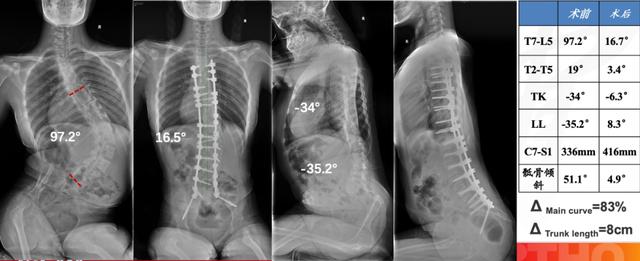

姗姗术前脊柱全长X线

武姗姗手术前后脊柱X光片对比